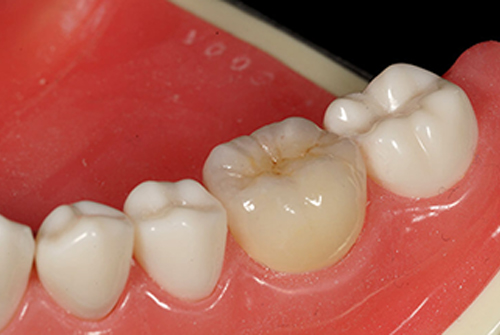

オールセラミック:

e-MAXインレーになります。こちら見た目硬さなど現在セラミックインレーの中で非常に多く使用されている材質になります。